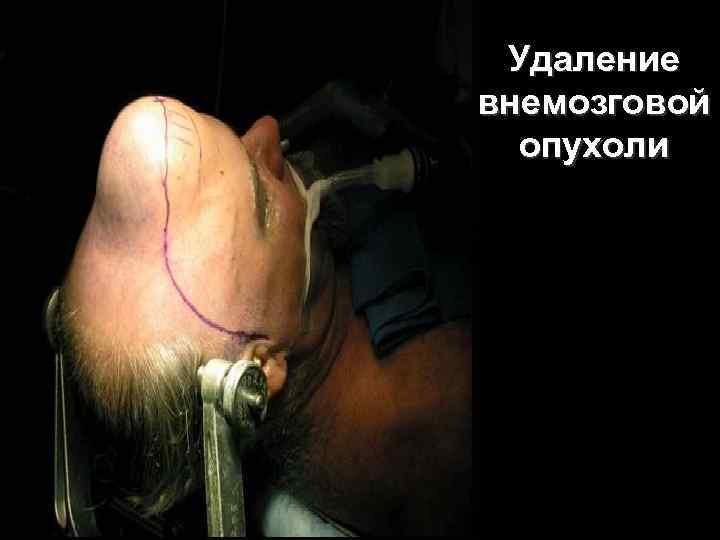

Удаление внемозговой опухоли 62